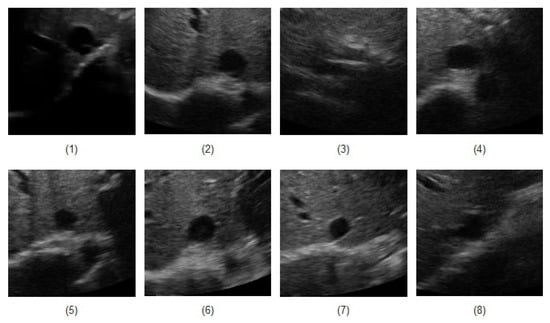

Ultrasound videos from eight healthy subjects (The data was actually collected from twenty subjects, but only for eight cases, the manual measurement seemed reliable to be used as the ground truth). were collected with the IVC imaged in the transverse plane using a portable ultrasound (M-Turbo, Sonosite-FujiFilm) and a phased-array probe (1–5 MHz). Each video has a frame rate of 30 fps, scan depth of 19 cm, and a duration of 15 s (450 frames/clip). Figure 5 depicts the first frame of all eight subjects. In Figure 5, one can see that an IVC image can have different shapes and qualities. For instance, in the clip no. (1), although part of the image is shadowed, but the IVC edges are almost visible. The IVC videos for the clips nos. (3) and (8) show the lowest quality as the IVC is almost collapsed in the former one and it vanishes after the initial frames in the latter one (this is not seen in this image as it is only the first frame of the video).

Figure 5.

The first frame of all eight IVC videos.